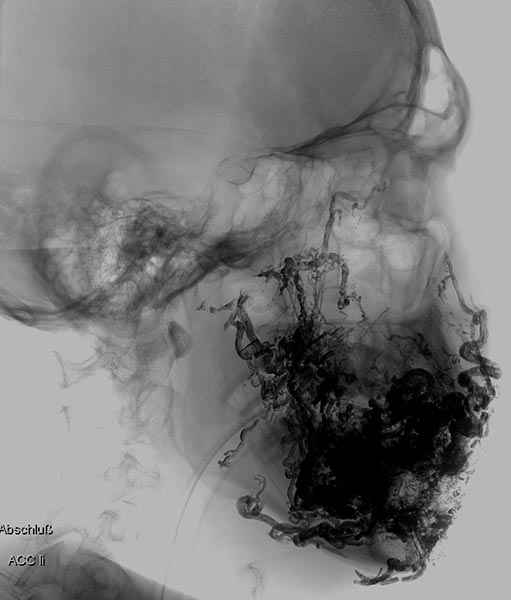

Auffüllung des gesamten Nidus der AVM mittels Ethylen-Vinyl Alkohol-Kopolymer, das in dem hier dargestellten Röntgenbild (a.-p.) als schwarzer, netzartiger röntgendichter Ausguss (sogenannter Cast) innerhalb der verschlossenen AVM-Gefäße sichtbar wird.

Auffüllung des gesamten Nidus der AVM mittels Ethylen-Vinyl-Alkohol-Kopolymer, das in dem hier dargestellten Röntgenbild (seitliche Ansicht) als schwarzer, netzartiger röntgendichter Ausguss (sogenannter Cast) innerhalb der verschlossenen AVM-Gefäße sichtbar wird.

In der Spätphase der DSA (laterale Ansicht) über die linke A. carotis interna. Nach erfolgreicher mehrfacher Embolisation ist auch die Versorgung des Nidus der AVM über diese kritischen Äste verschlossen und die A. ophtalmica erhalten.